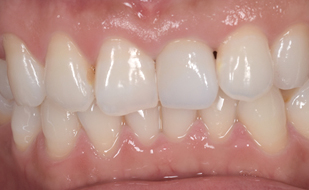

セラミッククラウン

の症例

| 主訴 | 前歯の形や大きさが気になる。 以前にかぶせ物を入れたが、 自分の顔に合っていない気がする。 |

| 年齢・性別 | 30代・女性 |

| 治療期間 | 2ヶ月 |

| リスク・副作用 | 噛む力が強い方の場合、セラミックが欠けてしまうことがあるので、就寝時にマウスピースを装着していただく必要があります。 |

| 治療内容 | ジルコニアボンドクラウンを用いて、 強度も審美も最高のもので、 歯茎の高さも合わせて完成させる。 |

| 治療費用 | 5,500円(税込)×4 (プロビジョナルレストレーション(仮歯)×4本) 歯ぐきの手術 55,000円(税込) |

| 治療方針 | 左右の歯のバランスを同じ数値で シンメトリーとする。 |

| 特記事項 | 回数かかっても良いので、 キレイに美しく仕上げて欲しい。 |